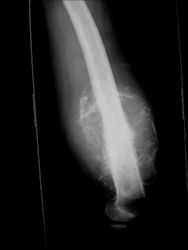

Gross Pathology: Conventional Osteosarcoma

These are examples of the gross pathology specimens of resected conventional osteosarcoma, consisting of both bony and soft tissue areas. X-rays of the specimens are included.

- Osteosarcomas are composed of ossified or non-ossified tissue

- Ossified tissue is yellow-white and hard

- Less ossified tissue is soft and less yellow

- Non-ossified tissue is tan and fleshy

- Most (95%) of conventional osteosarcomas penetrate the cortex and form a large extraosseous soft tissue mass

- The lesion permeates the marrow spaces

- Osteosarcomas usually infiltrate the marrow several centimeters away from the main tumor mass

- Skip lesions may be apparent that are separated from the main tumor by normal marrow

- Osteosarcomas may also have cartilaginous components that appear as translucent lobules, and/or fibrous components that are tan, soft to firm rubbery areas

- Osteoblastic areas are usually white to yellow, firm, hard and gritty

- The consistency of the tumor depends on the amount of osteoid deposition, cartilaginous and fibrous areas

- Foci of hemorrhage and necrosis are common

- Periosteal reactions such as the Codman’s triangle are apparent at periphery of soft tissue mass

- Osteosarcomas rarely penetrate the growth plate grossly

- Invasion of the joint is uncommon but can occur by cortical penetration, joint capsule extension, or extension along cruciate ligaments

Gross Pathology: Osteosarcoma of Proximal Humerus

- originates from metaphysis of the proximal humerus, extends into surrounding soft tissues

- large soft tissue component that is crossing the glenohumeral joint

- was removed via an extra-articular resection, including scapula (Tikhoff-Linberg resection)